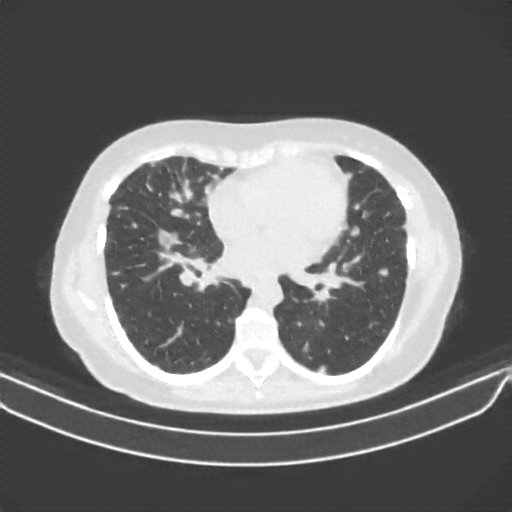

Targeted Slice 70 - Lung Window Analysis (Generated vs Real Venous)

0.752

Lung SSIM

110.9

Lung RMSE

46.5

Lung MAE

Average Lung Window Metrics Across All Slices (40 slices) - Generated vs Real Venous

0.745

Lung SSIM (Avg)

111.4

Lung RMSE (Avg)

45.4

Lung MAE (Avg)

Generated VENOUS CT scan (A→B translation)

Lung window (WL -600, WW 1500 β†’ Low βˆ’1350, High +150)